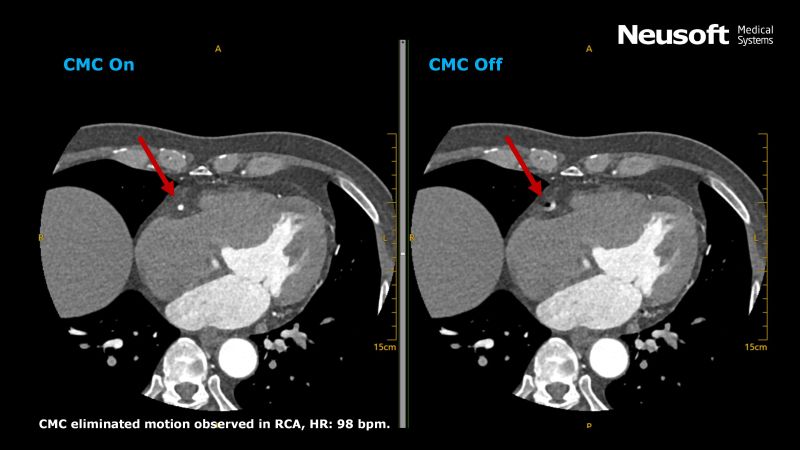

Exciting news! We are delighted to announce our advanced motion-correction technology, Coronary Motion Clear (CMC), which is one of our latest AI-enabled techniques developed by Neusoft Medical. This time, we have developed a sophisticated reconstruction approach using a three-dimensional mathematical model to depict the cardiac phase following movement and complement adaptive motion-correction reconstruction techniques. Together with streamlined One-Click design, you will experience an effective and precise generation of exquisite motion-corrected images.

After applying our latest version of CMC algorithm, we observed a significant improvement in image quality of the coronary artery compared to standard cardiac reconstructions. The image below depicts a middle-aged patient who was admitted with chest pain and shortness of breath and underwent a Cardiac CTA Scan on NeuViz Epoch that imaged the entire heart in one cardiac cycle for coronary artery evaluation (Average HR: 101 bpm). The right coronary artery appeared continuous and had excellent visualization throughout the scan after using one-click CMC processing. The radiation dose delivered during the CTA procedure was reported as low as 8.4 CTDI due to our introduction of AI-based Deep Learning Reconstruction technology, ClearInfinity, while maintaining image quality.